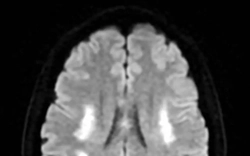

• Nam sinh trung học sốt 5 ngày rồi tử vong, bác sĩ cảnh báo: Bệnh phổ biến nhưng không thể xem nhẹ

Nam sinh trung học sốt 5 ngày rồi tử vong, bác sĩ cảnh báo: Bệnh phổ biến nhưng không thể xem nhẹ

Nam sinh xuất hiện sốt và nhiều biểu hiện khó chịu nhưng trì hoãn điều trị suốt 5 ngày. Khi được gia đình đưa vào khoa cấp cứu, em đã trong tình trạng kiệt sức toàn thân. Kết quả kiểm tra khiến bác sĩ không khỏi bàng hoàng.